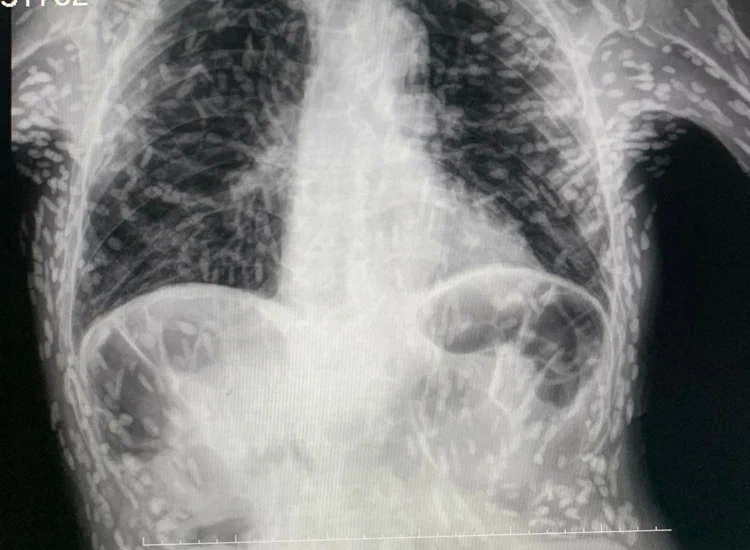

Недавно бразильский медицинский работник вызвал шок у множества пользователей социальных сетей, опубликовав рентгеновский снимок мужчины, страдающего цистицеркозом. Рентгеновский снимок показывал, что тело пациента содержит множество кальцинированных яиц ленточного червя! Один из ординаторов больницы Hospital das Clínicas в Ботукату, доктор Витор Борин де Соуза, поделился рентгеновским снимком пациента, чтобы продемонстрировать своим подписчикам, насколько серьезным может быть заражение ленточным червем. Врач объяснил, что белые пятна, которые были видны на животе и руках пациента, представляют собой кальцинированные яйца ленточного червя, вызванные инфекцией обычным кишечным паразитом. К счастью, эти яйца не представляли угрозы для пациента, который обратился за медицинской помощью из-за постоянного кашля, так как они были кальцинированными и неспособными к развитию. Несмотря на то, что эти кальцинированные цистицерки не причиняли дискомфорта мужчине и не представляли опасности для ег

Бразильский медик после ренгтненовского исследования был просто шокирован! У пациента тело было заражено яйцами ленточного червя